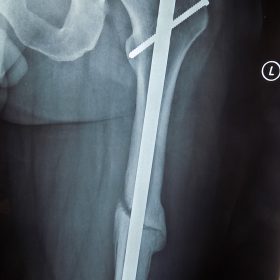

Τα κατάγματα της Διάφυσης των οστών της κνήμης και του Μηριαίου οστού στη σύγχρονη ΟΡΘΡΟΠΑΙΔΙΚΗ αντιμετωπίζονται με ΕΝΔΟΜΥΕΛΙΚΗ ΗΛΩΣΗ.

Δύο τομές 3 εκατοστών και 1 εκατοστού αντιστοίχως για την εισαγωγή και το κλείδωμα του ήλου μέσα στο οστό. Η μέθοδος είναι κλειστή,σχεδόν αναίμακτη,διάρκειας 60 λεπτών,με τη βοήθεια C-ARM (τηλεόρασης).

Στον ασθενή παρέχεται οπτικό υλικό (όλα τα χειρουργικά στάδια) σε CD ή Στικάκι,λόγω της δυνατότητας καταγραφής του χειρουργείου από το C-ARM Ο ασθενής περπατάει άμεσα μετεγχειρητικά στις 5 ώρες μετά την επέμβαση και εξέρχεται από το νοσοκομείο σε 1 -2 ημέρες.